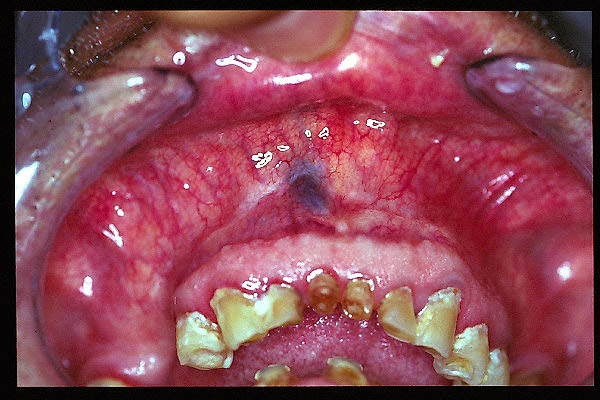

CM Nevus azul lingual